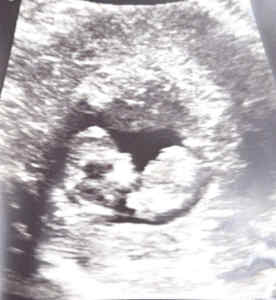

At this time we would like to thank everybody especially Doctor Shu. My wife is now 22 weeks pregnant. Thank you Dr. Shu for giving us the opportunity to bring another child into the world. As you can see this is an ultra sound picture from 4/25/2019. We have a more recent one revealing the sex of the baby. We are waiting until the reveal party to find out if we have a boy or a girl.